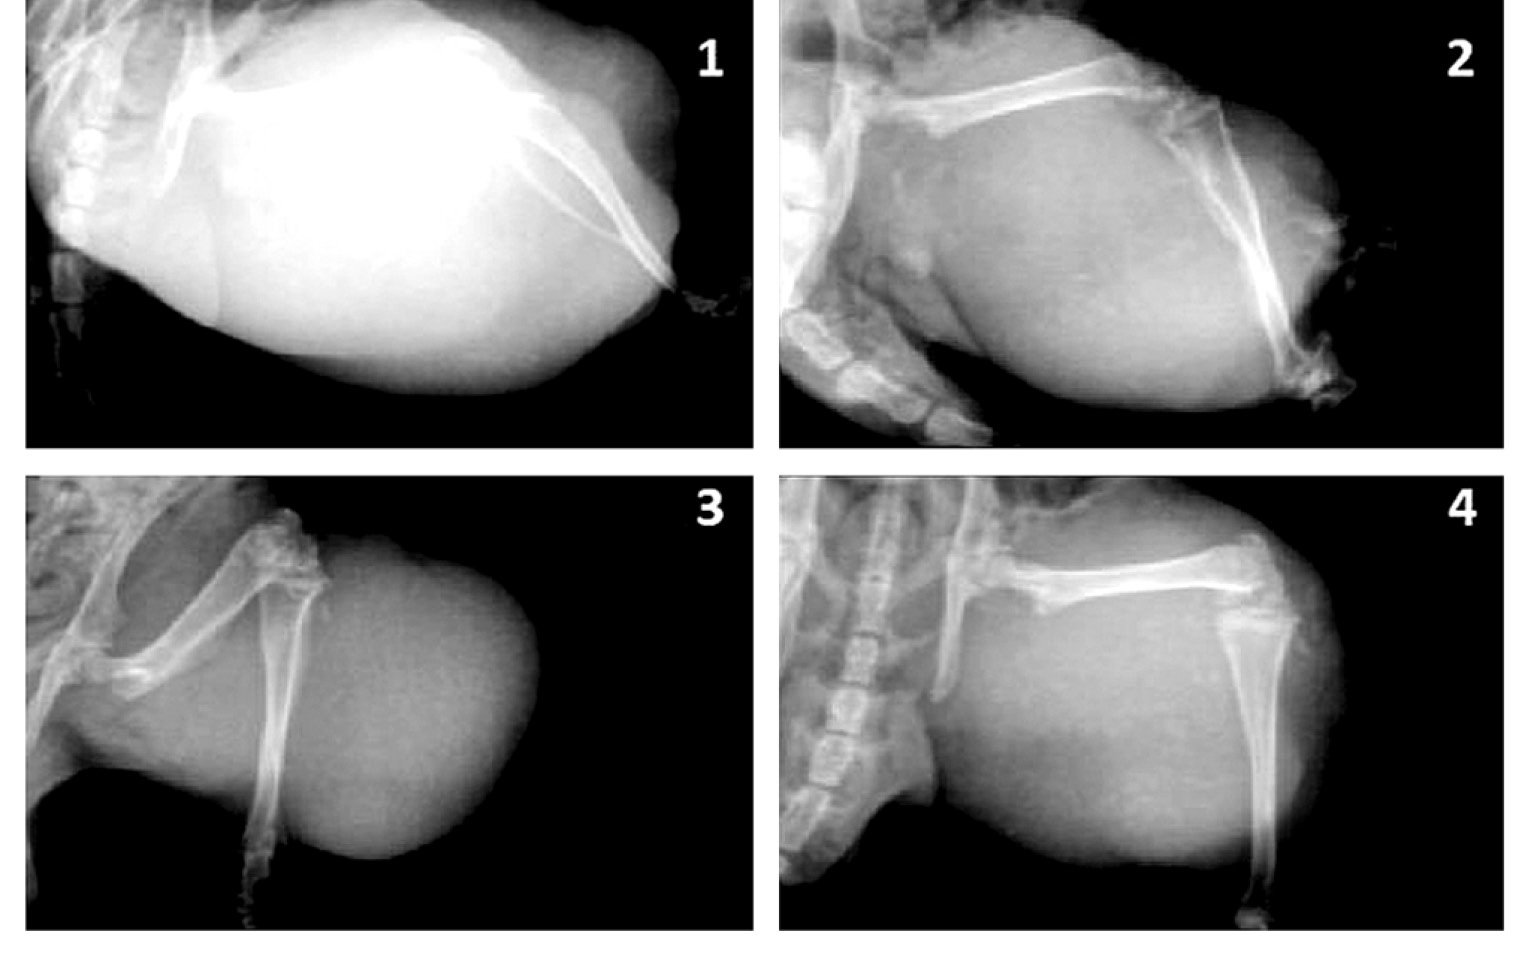

КТ-исследование и рентгенография при применении наносистем

Исследование in vitro показало выраженное контрастирование. Плотность препарата составила от –54 до –120 единиц по шкале Хаунсфилда (HU), что соответствует плотности жировой/соединительной ткани. Изучение in vivo в диапазоне доз показало не зависящее от дозы выраженное контрастирование сосудистого русла опухоли. Плотность сосудов опухоли составила от –47 до –80 HU при плотности ткани опухоли от –24 до –26 HU. МНЧ показали выраженные и стойкие контрастирующие способности по результатам КТ-исследования. Контрастирование сосудов, выявленное через 30 мин после в/а введения, сохранялось в течение 14 дней наблюдения. Длительное сохранение контрастирующего эффекта при КТ-исследовании свидетельствует о стабилизации наносистем или МНЧ в сосудах опухоли (рис. 4), тогда как метод рентгенографии (рис. 5) не позволяет детектировать частицы.

Рис. 5. Рентгенологическое исследование через 30 мин после введения наносистем на основе магнитных наночастиц и человеческого сывороточного альбумина в количестве 40 мкг по магнитным наночастицам (1) и через 14 дней после введения наносистем в количестве 20 мкг (2), 40 мкг (3) и 60 мкг (4) по магнитным наночастицам.

Fig. 5. X-ray imaging after 30 minutes after injection of nanosystems corresponding to 40 μg of magnetic nanoparticles (1) and 14 days after injection of nanosystems corresponding to 20 μg (3), 40 μg (3) and 60 μg (4) of magnetic nanoparticles.